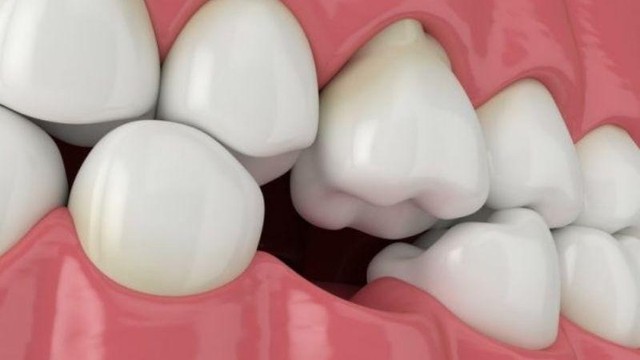

/https://cms-prod.s3-sgn09.fptcloud.com/tieu_xuong_rang_nguy_hiem_nhu_the_nao_den_suc_khoe_S_Hj_QR_1680281916_3bb85dd0db.jpg)

Mất xương hàm sau khi mất răng là một hậu quả nghiêm trọng, gây ảnh hưởng đến tính thẩm mỹ và chức năng ăn nhai. Điều này có thể gây ảnh hưởng nghiêm trọng đến bệnh lý tiêu xương ổ răng. Vậy tiêu xương răng nguy hiểm thế nào đến sức khỏe?